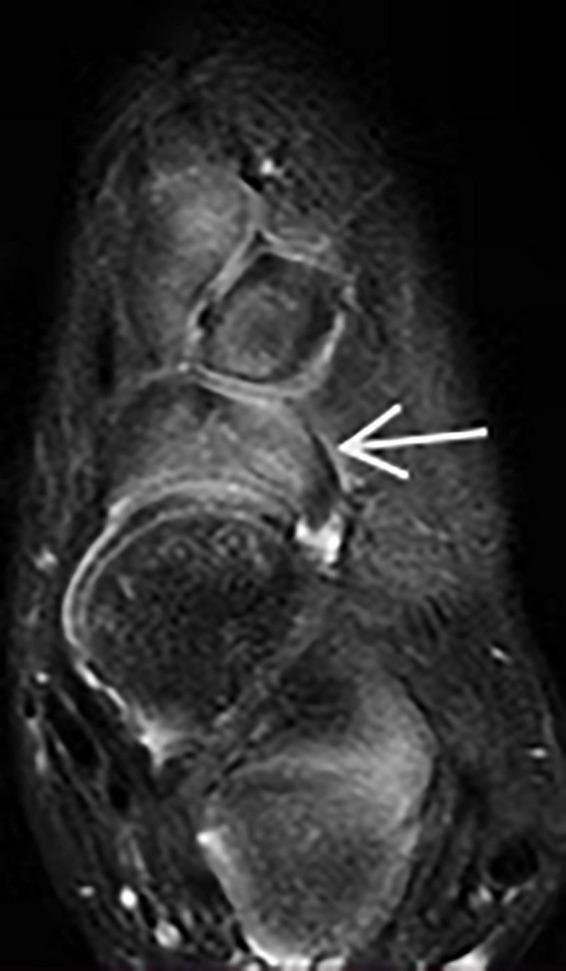

In total, 15 cases (twelve boys and three girls) with clubfeet were examined by using MRI. Twelve cases had unilateral and three had bilateral involvement (eleven left clubfeet and seven right clubfeet), giving a total of eighteen clubfeet when compared with twelve normal feet. The mean age of patients at examination was 47.7 months (8-96 months). The recovery of the corrected clubfoot in these patients met the goals of Ponseti treatment (functional, normal looking, pain-free, and plantigrade foot). Before Ponseti treatment, the mean Pirani score of clubfoot was 5.5 (5-6). During this follow-up, the Pirani score was 0.07 (0-0.05). The results of the MRI indicated that only the transverse talonavicular angle showed a significant difference between the treated clubfeet and the normal feet ( < 0.001). One case had dorsal talonavicular subluxation in the sagittal plane and had the lateral subluxation of the navicular in the transverse plane, which has never been reported in previous studies.

Although the appearance and function of clubfoot were recovered well after the Ponseti method, the results of MRI indicated that the Ponseti method successfully corrected the varus, cavus, and equinus deformities and incompletely corrected the adduction deformity regarding transverse talonavicular angle. At the same time, the Ponseti method may cause dorsal talonavicular subluxation in the sagittal plane and lateral subluxation of the navicular in the transverse plane on MRI.

总共对15例(12例男孩和3例女孩)马蹄内翻足患儿进行了MRI检查。12例为单侧受累,3例为双侧受累(11例左侧马蹄内翻足和7例右侧马蹄内翻足),与12例正常足相比,共有18例马蹄内翻足。检查时患者的平均年龄为47.7个月(8 - 96个月)。这些患者矫正后的马蹄内翻足恢复情况达到了庞塞蒂治疗的目标(功能正常、外观正常、无痛且足能放平)。在庞塞蒂治疗前,马蹄内翻足的平均皮拉尼评分为5.5(5 - 6)。在此次随访期间,皮拉尼评分为0.07(0 - 0.05)。MRI结果表明,仅横断面距舟角在治疗后的马蹄内翻足与正常足之间存在显著差异(<0.001)。1例在矢状面有距舟背侧半脱位,在横断面有舟骨外侧半脱位,这在以往研究中从未有过报道。

尽管采用庞塞蒂方法后马蹄内翻足的外观和功能恢复良好,但MRI结果表明,庞塞蒂方法成功矫正了内翻、高弓和马蹄畸形,但在横断面距舟角方面内收畸形未完全矫正。同时,庞塞蒂方法在MRI上可能导致矢状面距舟背侧半脱位和横断面舟骨外侧半脱位。